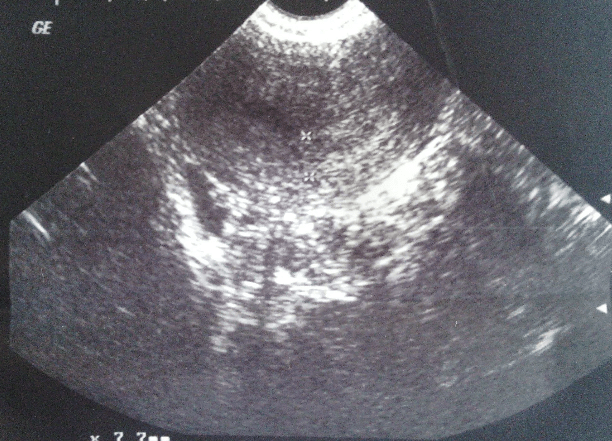

葡萄胎(图)-妇科超声-搜狐博客

正常的超声影像葡萄胎的超声影像超声可见子宫呈蜂窝状,且血hcg持续